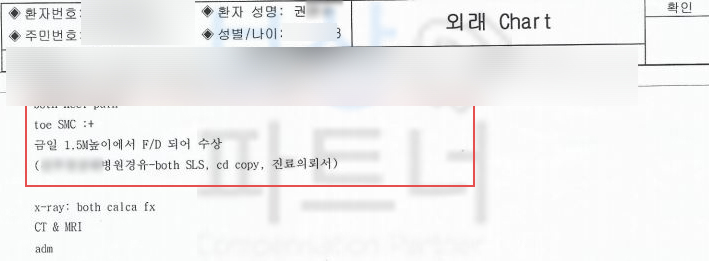

권@@님은 1.5M 높이에서 떨어지는 추락 사고를 당하셨습니다.

위 사고로 정밀검사를 진행하게 되었고 그 결과

진단서를 보시면

양 발의 종골(calcaneus) 골절

S9200 진단을 받으셨습니다. 먼저 일하시다 재해를 당하셨다면 의무 보험인 산재 보험에서 요양급여, 휴업급여, 장해급여까지 보상 가능하십니다. 의뢰인의 경우 이미 산재처리를 하여 저희 보상 파트너에서는 고객님께서 개인적으로 가입하신 보험 증권을 확인했고